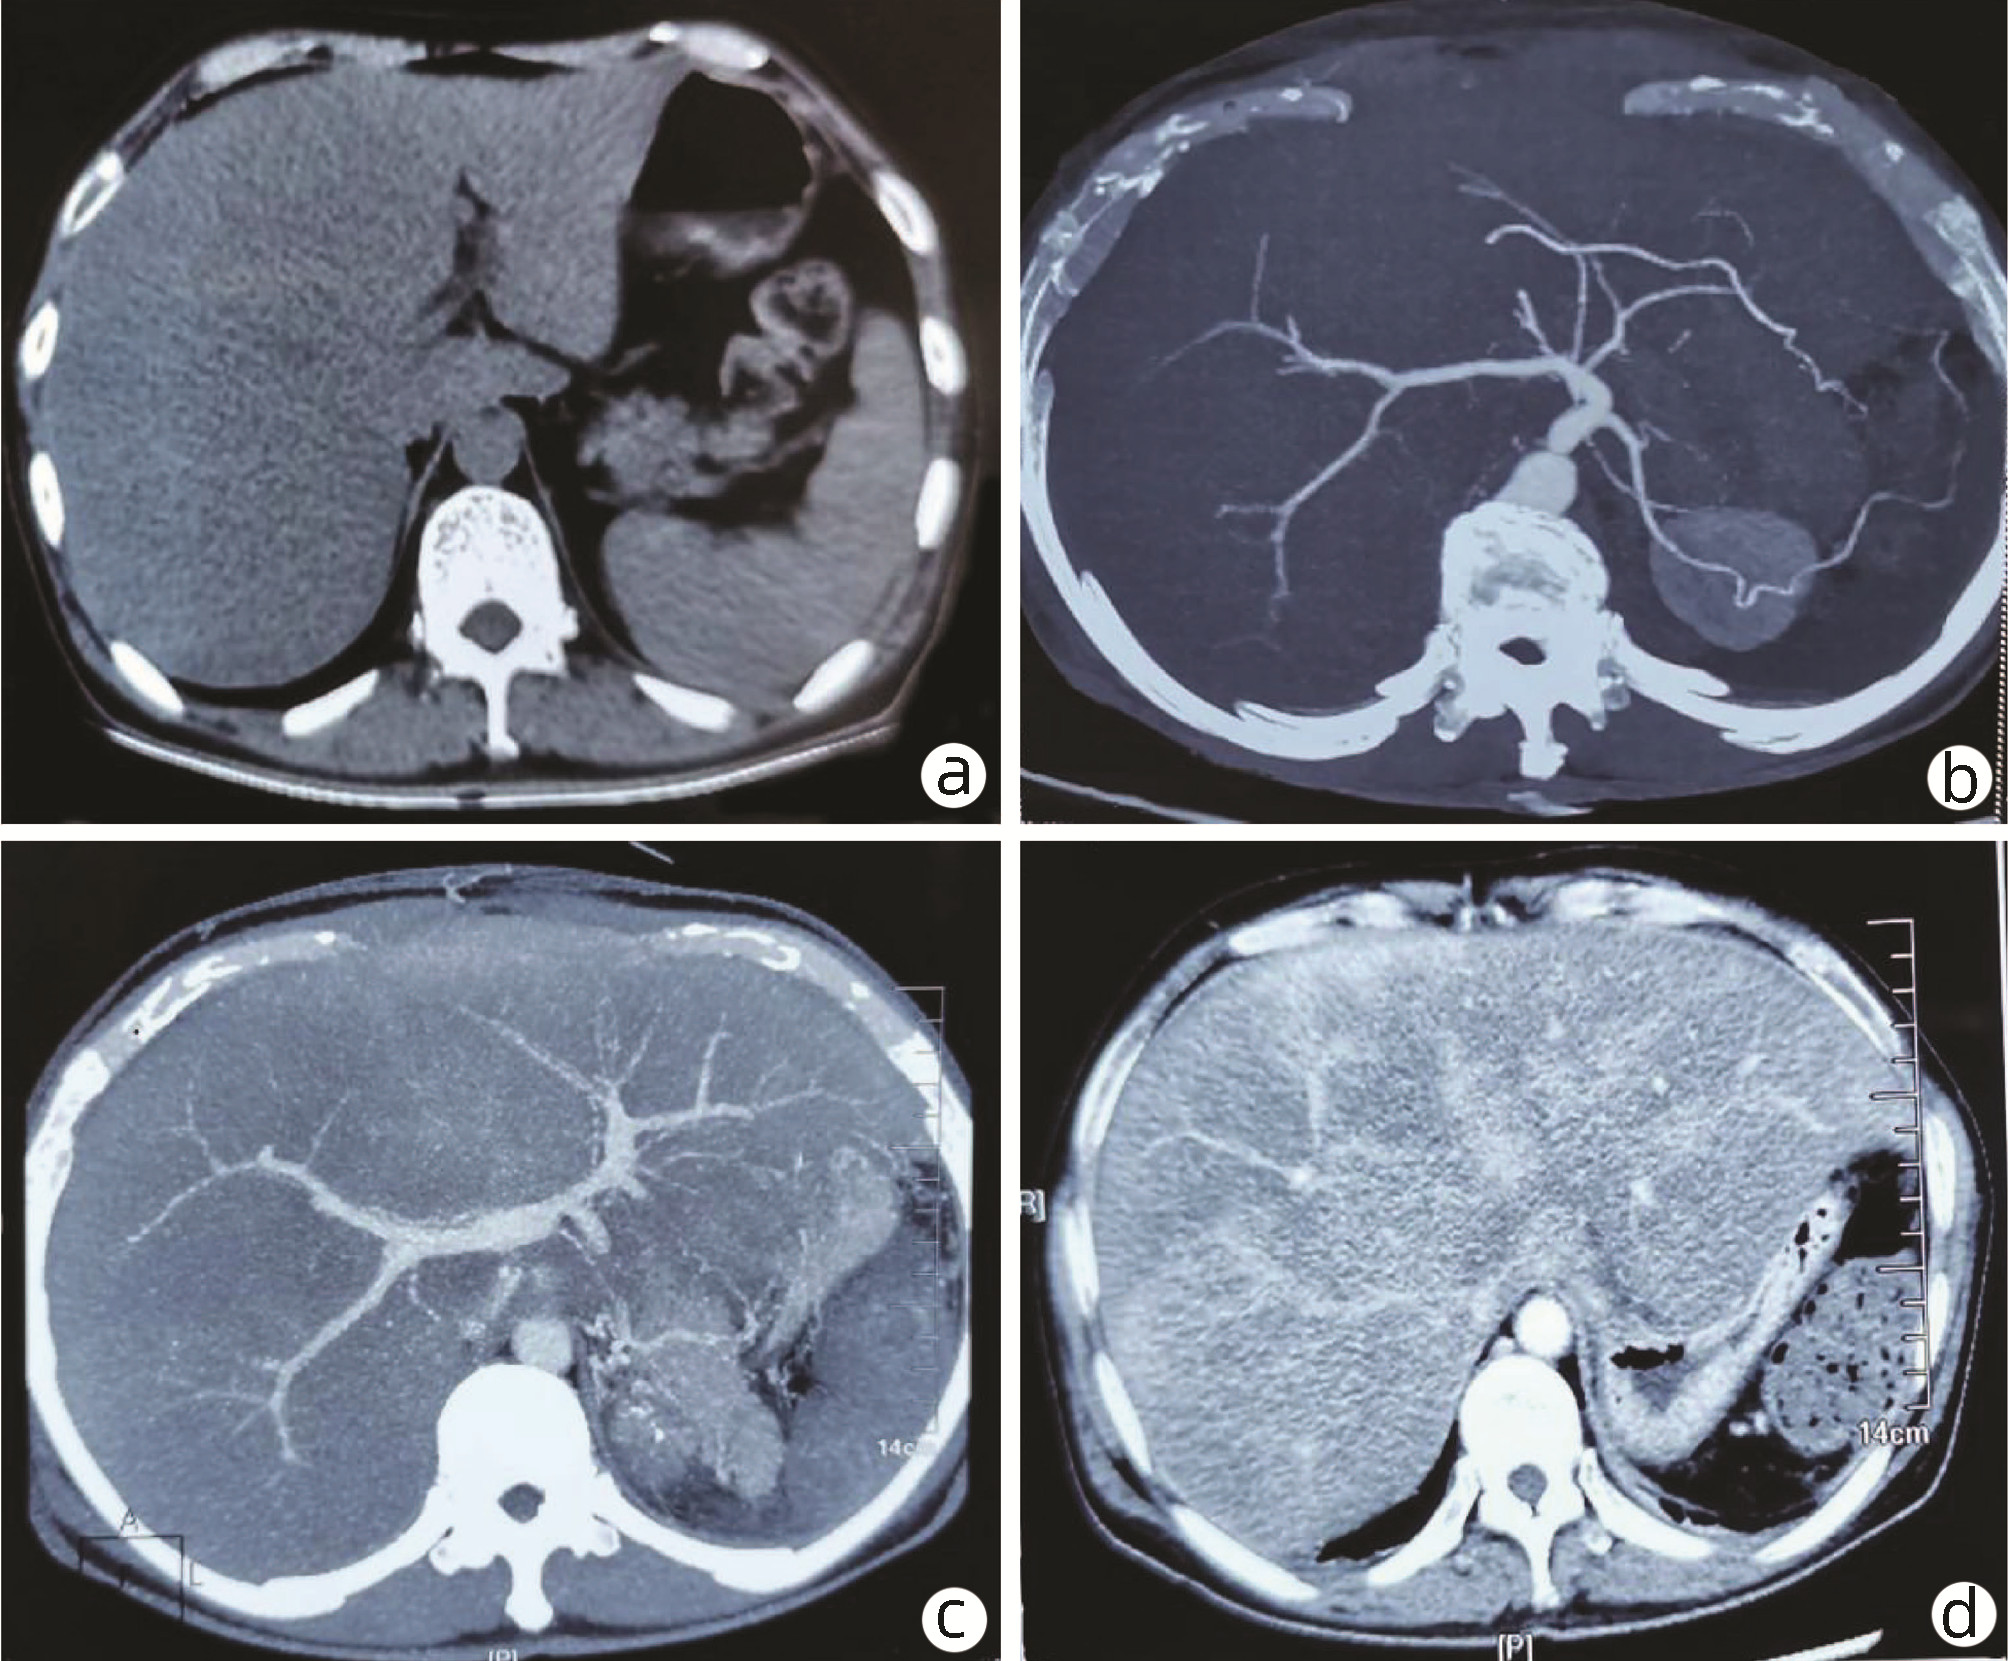

A case of systemic light-chain amyloidosis with fatal spontaneous splenic rupture

Duo LI, Yingren ZHAO, Hongmei CHEN

2022, 38(8): 1883-1885. DOI: 10.3969/j.issn.1001-5256.2022.08.032

Abstract(727) HTML (255) PDF (2823KB)(68)

Abstract: